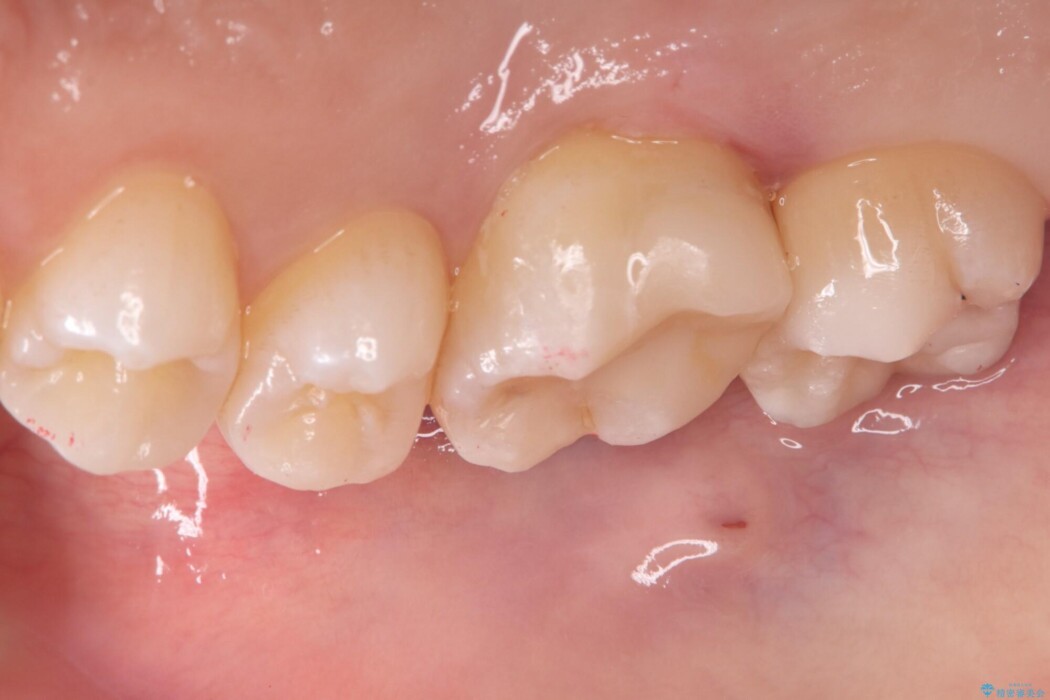

治療後について

セラミックアンレーセット時は、ラバーダム防湿を行っています。